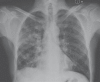

Figure 3

Chest radiograph after recovery